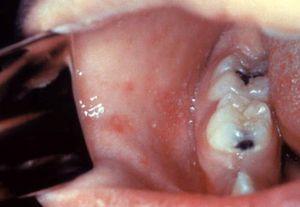

홍역의 전구기는 발진이 나타나기 시작하는 시기로, 기침, 콧물, 결막염의 3C 증상이 나타난다. 또한, 경미한 발열이 동반된다. 이 시기에는 어금니 옆 구강 점막에 빨간색의 코플릭 반점이 나타나는 것이 특징이다.[30][67] 코플릭 반점은 "붉은 배경 위의 소금 알갱이"처럼 보이는 작은 흰색 반점으로,[31] 홍역 진단에 중요한 단서가 되지만 일시적이어서 관찰이 어려울 수 있다.[30]전구기는 3~4일간 지속되며, 이 시기에 전염성이 가장 강하다. 38℃ 전후의 감기와 비슷한 증상(발열, 권태감, 상기도염 증상)과 결막염 증상이 2~4일 지속되다가 일시적으로 열이 내린다. 전구기 후반, 발진이 나타나기 1~2일 전에 구강 점막 어금니 부근에 지름 1mm 정도의 약간 부풀어 오른 백색 소반점(코플릭 반점)이 생긴다. 눈에는 다량의 눈곱, 눈물, 눈의 통증이 나타나며, 심한 경우 각막에 궤양이 생기거나 구멍이 나서 실명에 이르기도 한다.[215]

홍역의 증상은 일반적으로 바이러스에 노출된 후 10~14일 후에 나타난다.[59][67] 전형적인 증상으로는 4일 동안 지속되는 발열(4D)과 기침, 콧물(감기, 발열, 재채기), 결막염(충혈된 눈)을 동반하는 3C 증상, 그리고 반점구진성 발진이 있다.[30] 발열은 흔하게 나타나며, 대략 1주일 정도 지속된다. 홍역에서 나타나는 발열은 40°C까지 오르기도 한다.[179]입 안쪽에서 관찰되는 코플릭 반점은 홍역 진단에 유용하지만, 일시적으로 나타나기 때문에 자주 관찰되지는 않는다.[30] 코플릭 반점은 작고 흰색을 띠는 반점으로, 주로 어금니 맞은편 뺨 안쪽에 생긴다.[67] 이는 "붉은 배경 위의 소금 알갱이"와 같은 모양을 하고 있다.[31] 환자의 전염성이 가장 강해지기 전에 이러한 반점을 발견하면 질병 확산을 줄이는 데 도움이 될 수 있다.[32]